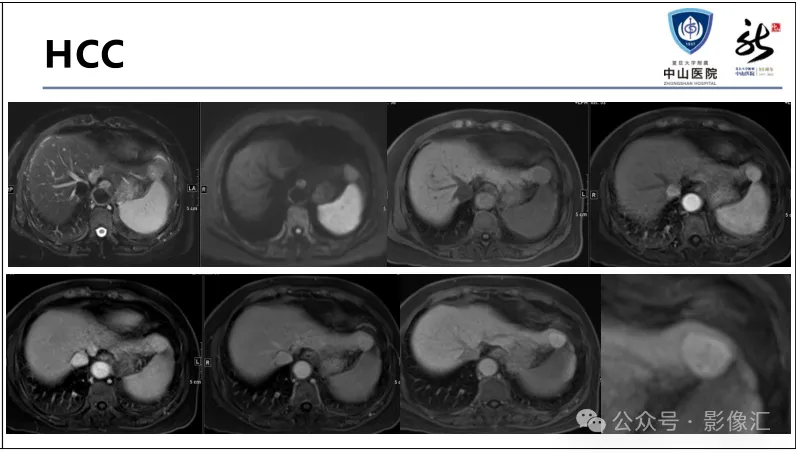

>【精品课件】如何正确判读肝胆特异性对比剂增强图像?

肝胆特异性对比剂增强肝胆图像判读方法与策略,课件来源于网络,作者复旦大学附属中山医院放射科饶圣祥教授。